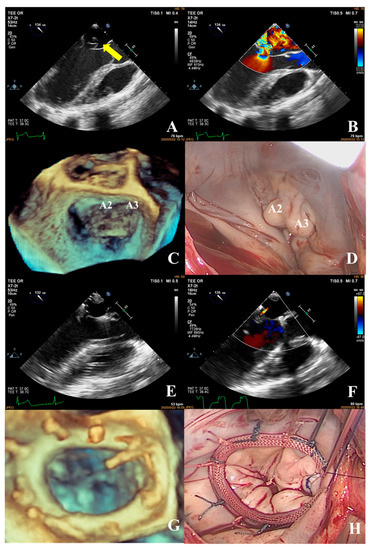

Prediction of Surgical Approach in Mitral Valve Disease by XGBoost Algorithm Based on Echocardiographic Features

In this study, we aimed to develop a prediction model to assist surgeons in choosing an appropriate surgical approach for mitral valve disease patients. We retrospectively analyzed a total of 143 patients who underwent surgery for mitral valve disease. The XGBoost algorithm was [...] Read more.

In this study, we aimed to develop a prediction model to assist surgeons in choosing an appropriate surgical approach for mitral valve disease patients. We retrospectively analyzed a total of 143 patients who underwent surgery for mitral valve disease. The XGBoost algorithm was used to establish a predictive model to decide a surgical approach (mitral valve repair or replacement) based on the echocardiographic features of the mitral valve apparatus, such as leaflets, the annulus, and sub-valvular structures. The results showed that the accuracy of the predictive model was 81.09% in predicting the appropriate surgical approach based on the patient’s preoperative echocardiography. The result of the predictive model was superior to the traditional complexity score (81.09% vs. 75%). Additionally, the predictive model showed that the three main factors affecting the choice of surgical approach were leaflet restriction, calcification of the leaflet, and perforation or cleft of the leaflet. We developed a novel predictive model using the XGBoost algorithm based on echocardiographic features to assist surgeons in choosing an appropriate surgical approach for patients with mitral valve disease. Full article